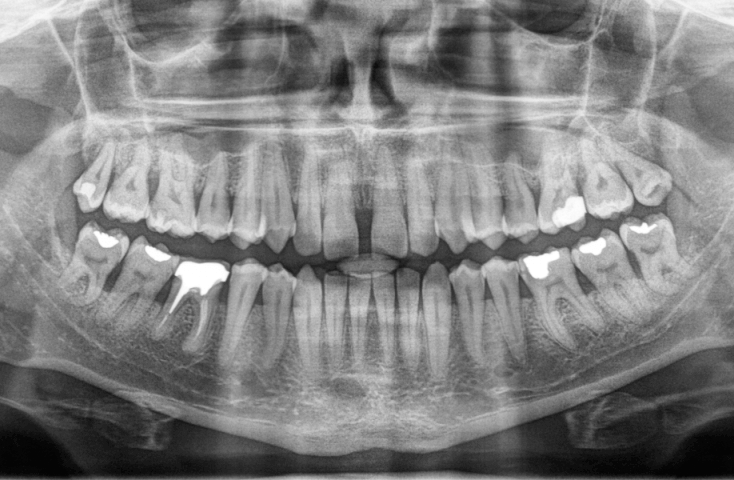

Pantomogram

Podstawowe badanie RTG w stomatologii. Zdjęcie pantomograficzne zębów, kości szczęki, żuchwy oraz stawów skroniowo-żuchwowych i zatok szczękowych (2D). Pozwala ocenić stan zdrowia przyzębia oraz wszystkich zębów.